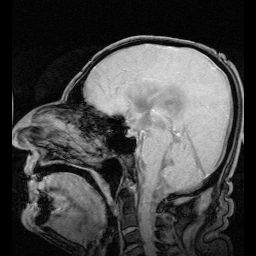

뇌실계는 뇌척수액이 순환하는 뇌 속의 공간으로, 4개의 뇌실과 이를 연결하는 통로로 구성된다. 가쪽뇌실, 셋째뇌실, 넷째뇌실로 이루어져 있으며, 뇌실사이구멍, 중간뇌수도관, 정중공, 가쪽구멍을 통해 서로 연결된다. 뇌실계는 뇌척수액을 생성하고 순환시키며, 뇌를 물리적 충격으로부터 보호하고 뇌에 영양을 공급하는 역할을 한다. 뇌실계 관련 질환으로는 수두증, 수막염, 뇌실염 등이 있으며, 정신 분열증과 같은 정신 질환과도 연관될 수 있다.

| 뇌척수액 흐름 경로 | 가쪽뇌실 → 뇌실사이구멍 (몬로 구멍) → 제3뇌실 → 중뇌수도 (실비우스 수도) → 제4뇌실 제4뇌실에서 대부분의 뇌척수액은 거미막밑공간으로 흘러가고, 소량은 척수 중심관으로 들어감 |

뇌척수액은 주로 뇌실의 맥락얼기에서 생성되어 가쪽뇌실로부터 뇌실사이구멍을 통해 셋째뇌실로 이동한다. 이후 뇌줄기에 있는 중간뇌수도관을 통해 넷째뇌실로 들어간다.[24] 이 과정에서 맥락얼기의 동맥박동이 뇌척수액의 순환을 돕는다. 뇌척수액은 넷째뇌실에서부터 정중구멍과 가쪽오목의 가쪽구멍을 통해 거미막밑공간으로 유입된다. 이어서 소뇌숨뇌수조 및 다리뇌수조를 거쳐 서서히 이동하여 좌우 소뇌천막 사이의 간격을 통해 위로 올라온다. 이후 뇌척수액은 대뇌반구의 옆면을 따라 위로 순환한다. 척수로 간 뇌척수액은 계속해서 아래로 이동하여 말총 주위의 거미막밑공간에 분포한다. 허리천자는 이 부위에서 행한다.[24] 뇌척수액은 경막의 정맥굴, 특히 위시상정맥굴로 돌출된 거미막융모에서 주로 흡수된다.[24] 정맥굴로 들어간 뇌척수액은 목정맥을 거쳐 정맥계에 합류한다.